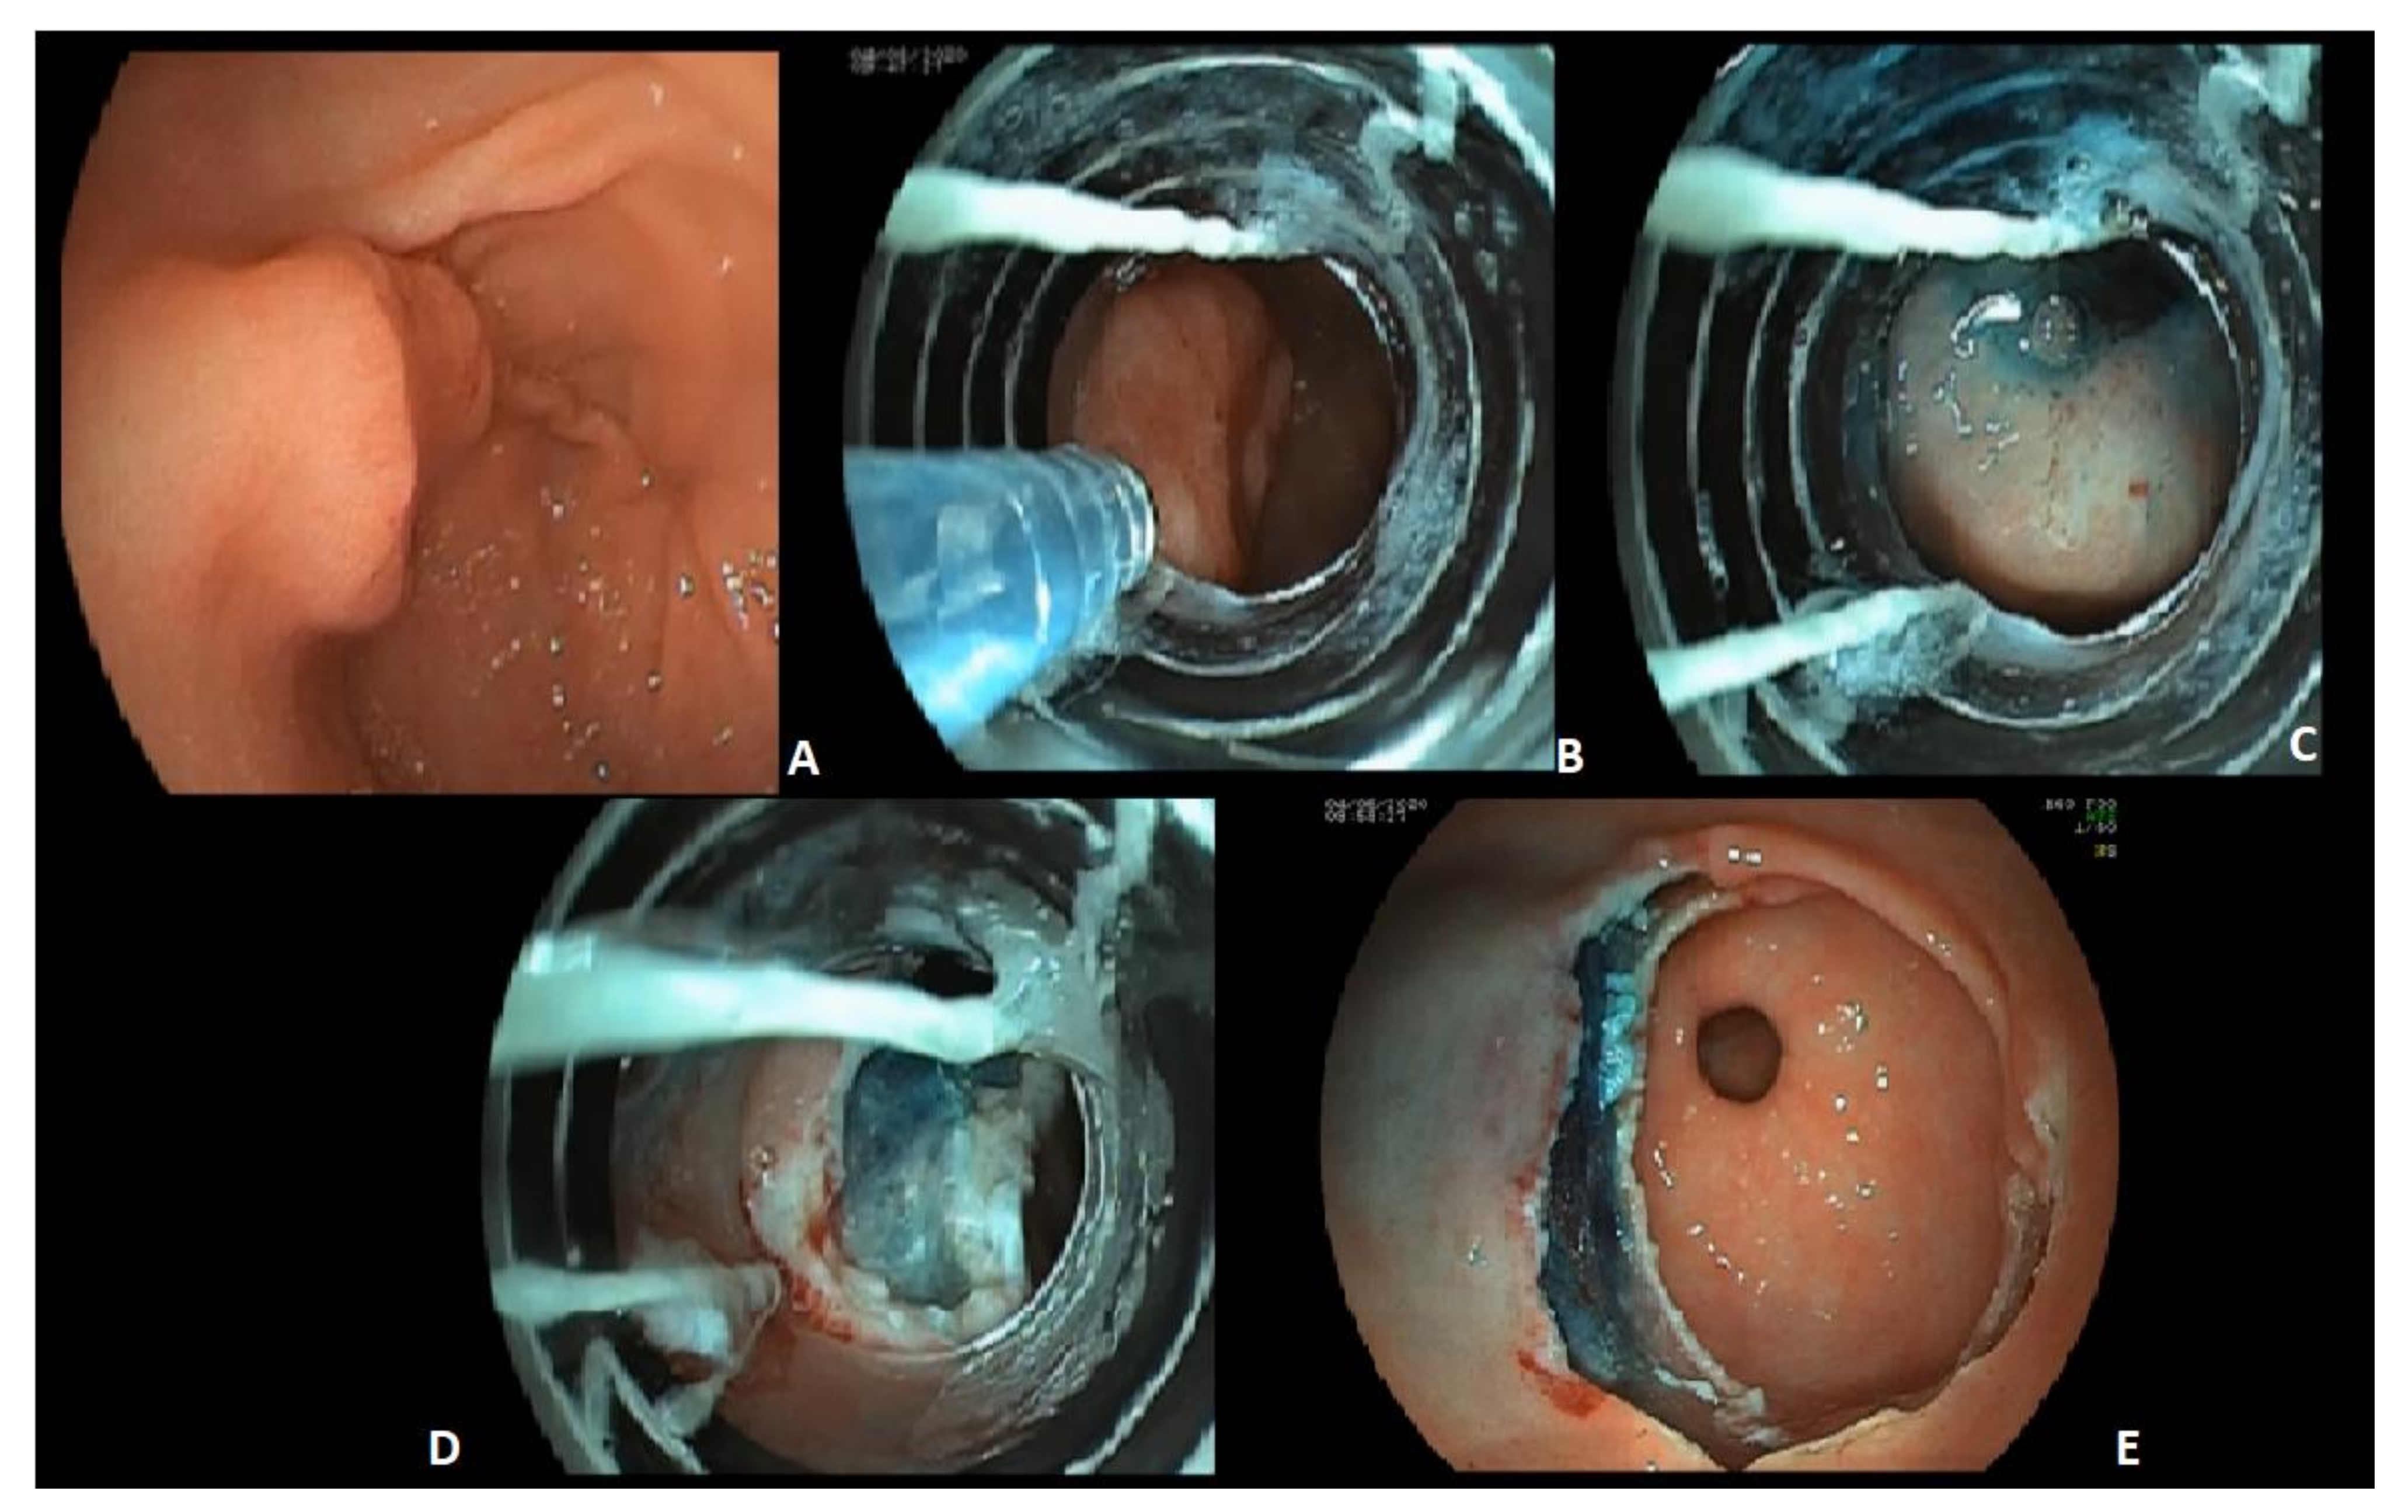

4.1.3. Endoscopic Mucosal Resection and Submucosal Dissection

- Tao, M.; Zhou, X.; Hu, M.; Pan, J. Endoscopic submucosal dissection versus endoscopic mucosal resection for patients with early gastric cancer: A meta-analysis. BMJ Open 2019, 9, e025803. [Google Scholar] [CrossRef]

- Zhao, Y.; Wang, C. Long-Term Clinical Efficacy and Perioperative Safety of Endoscopic Submucosal Dissection versus Endoscopic Mucosal Resection for Early Gastric Cancer: An Updated Meta-Analysis. BioMed Res. Int. 2018, 2018, 3152346. [Google Scholar] [CrossRef]

- Park, Y.-M.; Cho, E.; Kang, H.-Y.; Kim, J.-M. The effectiveness and safety of endoscopic submucosal dissection compared with endoscopic mucosal resection for early gastric cancer: A systematic review and metaanalysis. Surg. Endosc. 2011, 25, 2666–2677. [Google Scholar] [CrossRef]